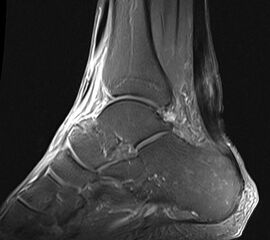

Schwere Veränderungen der Binnenstruktur der Achillessehne im MRT in den T2 gewichteten Aufnahmen als Korrelat einer ausgeprägten Achillodynie

Abbildung 7

Die Magnetresonanztomographie (MRT) hat insbesondere bei ansatznahen Beschwerden Ihren Stellenwert (Abb. 7). Sie kann ein begleitendes Knochenödem des Calcaneus wie auch ggf. eine Stressfraktur ausschließen helfen. Neben Signalalterationen insbesondere in der T2-Wichtung sind Nekrosen, Teilrupturen und begleitende Ödeme häufige Befunde, wie auch in 10% eine fettige Degeneration des M. gastrocnemius 28.